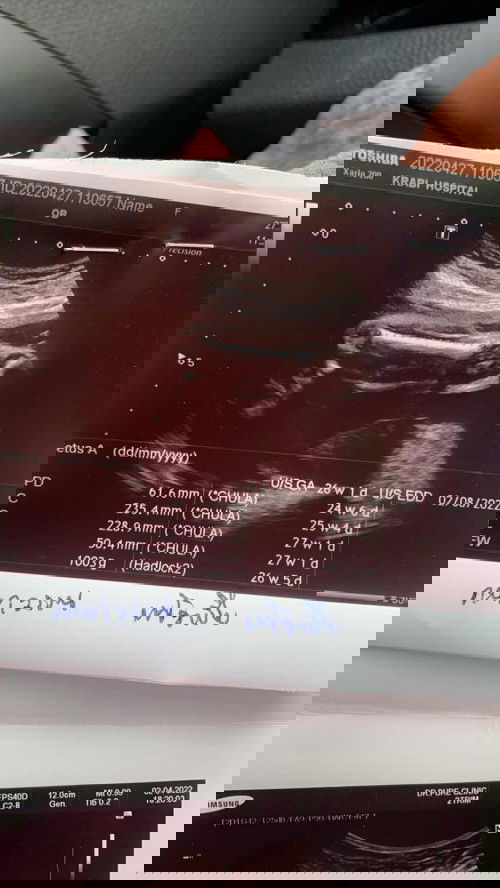

วันที่2เมษา ไปซาว คลีนิค น้องน้ำหนักน้อย 440 g เเล้ววันที่22เมษาไปซาว 791 g เเล้ววันที่27 ที่ผ่านมา น้องน้ำหนัก1,003 g น้องน้ำหนักดีมั้ยค่ะ หมอสั่งลดของหวานเเล้วค่ะ😂🥰#ท้องแรกคะ #ขอบคุณสำหรับคำตอบค่ะ